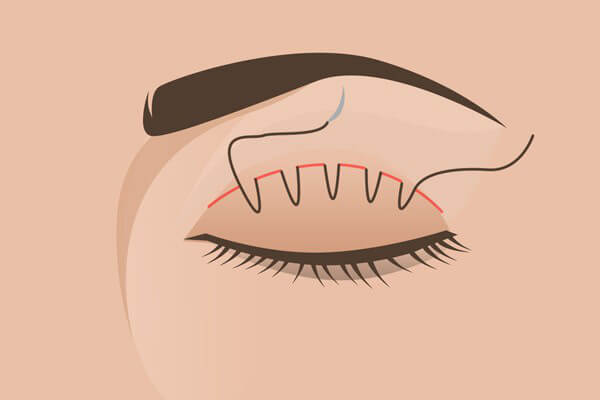

1. Phương pháp cắt mí

Phương pháp cắt mí là một cuộc tiểu phẫu nhỏ, thời gian mổ chỉ từ 30 đến 45 phút. Phương pháp này mang lại đôi mắt 2 mí vĩnh viễn và được biết như 1 kỹ thuật tạo mắt 2 mí phổ biến nhất từ trước tới nay.

Đầu tiên, các bác sĩ sẽ đo và vẽ viền mi mắt cho bạn rồi dùng dao, kéo rạch liên tục theo đường viền vừa vẽ. Tiếp theo, bác sĩ cắt bỏ một phần mô ở mi mắt…

… rồi tạo sự liên kết bằng cách khâu cân cơ nâng mi với da.

Cách cắt mi này mất nhiều thời gian nghỉ dưỡng nhưng sẽ mang lại hiệu quả lâu dài, phương pháp này sẽ để lại sẹo dễ nhìn thấy, tuy nhiên phần sẹo sẽ bị che khuất bởi nếp gấp mí, chỉ khi bạn nhắm mắt mọi người mới thấy được vết sẹo.